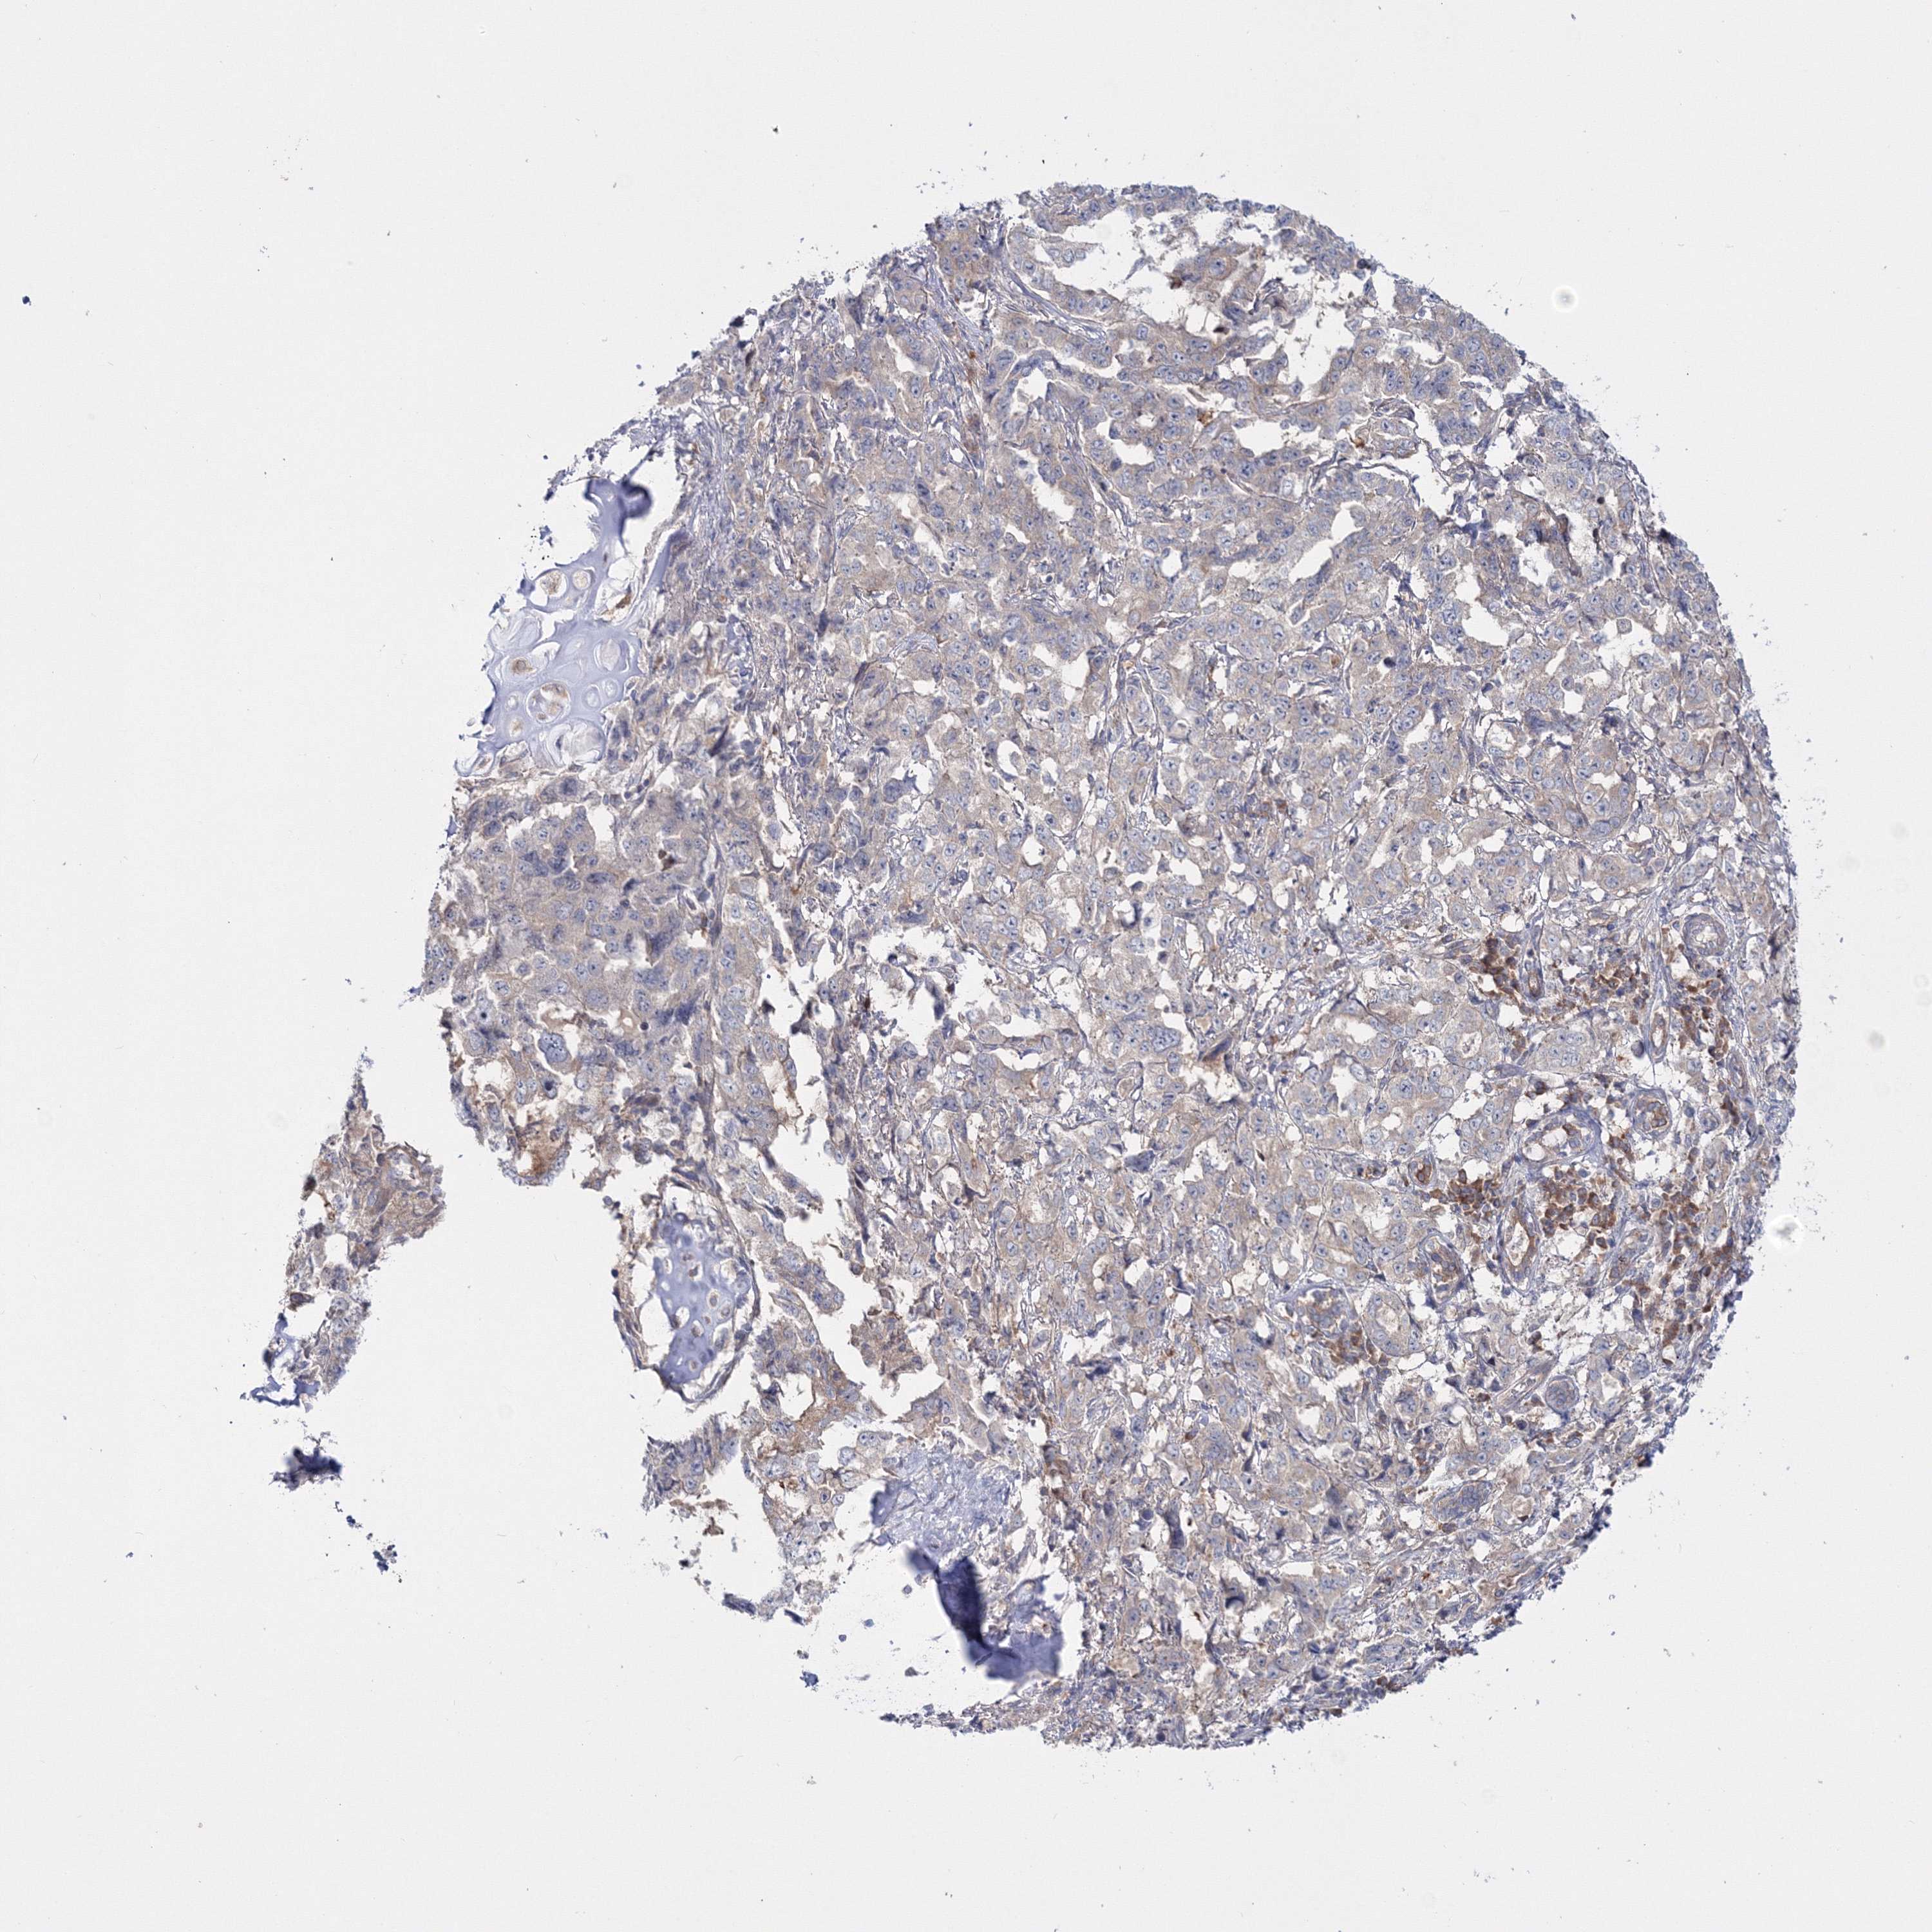

LUNG SQUAMOUS CELL CARCINOMA (TCGA) - Interactive survival scatter ploti

The Survival Scatter plot shows the clinical status (i.e. dead or alive) for all individuals in the patient cohort, based on the same data that underlies the corresponding Kaplan-Meier plots. Patients that are alive at last time for follow-up are shown in blue and patients who have died during the study are shown in red.

The x-axis shows the expression levels (FPKM) of the investigated gene in the tumor tissue at the time of diagnosis. The y-axis shows the follow-up time after diagnosis (years). Both axes are complimented with kernel density curves demonstrating the data density over the axes. The top density plot shows the expression levels (FPKM) distribution among dead (red) and alive patients (blue). The right density plot shows the data density of the survived years of dead patients with high and low expression levels respectively, stratified using the cutoff indicated by the vertical dashed line through the Survival Scatter plot. This cutoff is automatically defined based on the FPKM cutoff that minimizes the p-score. The cutoff can be changed by dragging the vertical line or by entering a cutoff value in the square labeled "Current cut-off".

Under the Survival Scatter plot the p-score landscape (black curve; left axis) is shown together with dead median separation (red curve; right axis). Dead median separation is the difference in median mRNA expression between patients who have died with high and low expression, respectively. It is calculated as follows: median FPKM expression of dead patients with high expression - median FPKM expression of dead patients with low expression. This is intended to aid the user in visually exploring custom cutoffs and the associated p-scores and dead median separation.

Individual patient data is displayed and can be filtered by clicking on one or more of the category buttons on the top of the page. Categories describing expression level and patient information include: high, low, alive, dead, female, male and tumor stages. The scale of the x-axis can be toggled between linear and log-scale by clicking on the "x log" button. Mouse-over function shows TCGA ID, patient information and mRNA expression (FPKM) for each patient.

& Survival analysisi

Kaplan-Meier plots summarize results from analysis of correlation between mRNA expression level and patient survival. Patients were divided based on level of expression into one of the two groups "low" (under cut off) or "high" (over cut off). X-axis shows time for survival (years) and y-axis shows the probability of survival, where 1.0 corresponds to 100 percent.

IPMK is not prognostic in Lung Squamous Cell Carcinoma (TCGA)

: 4.71